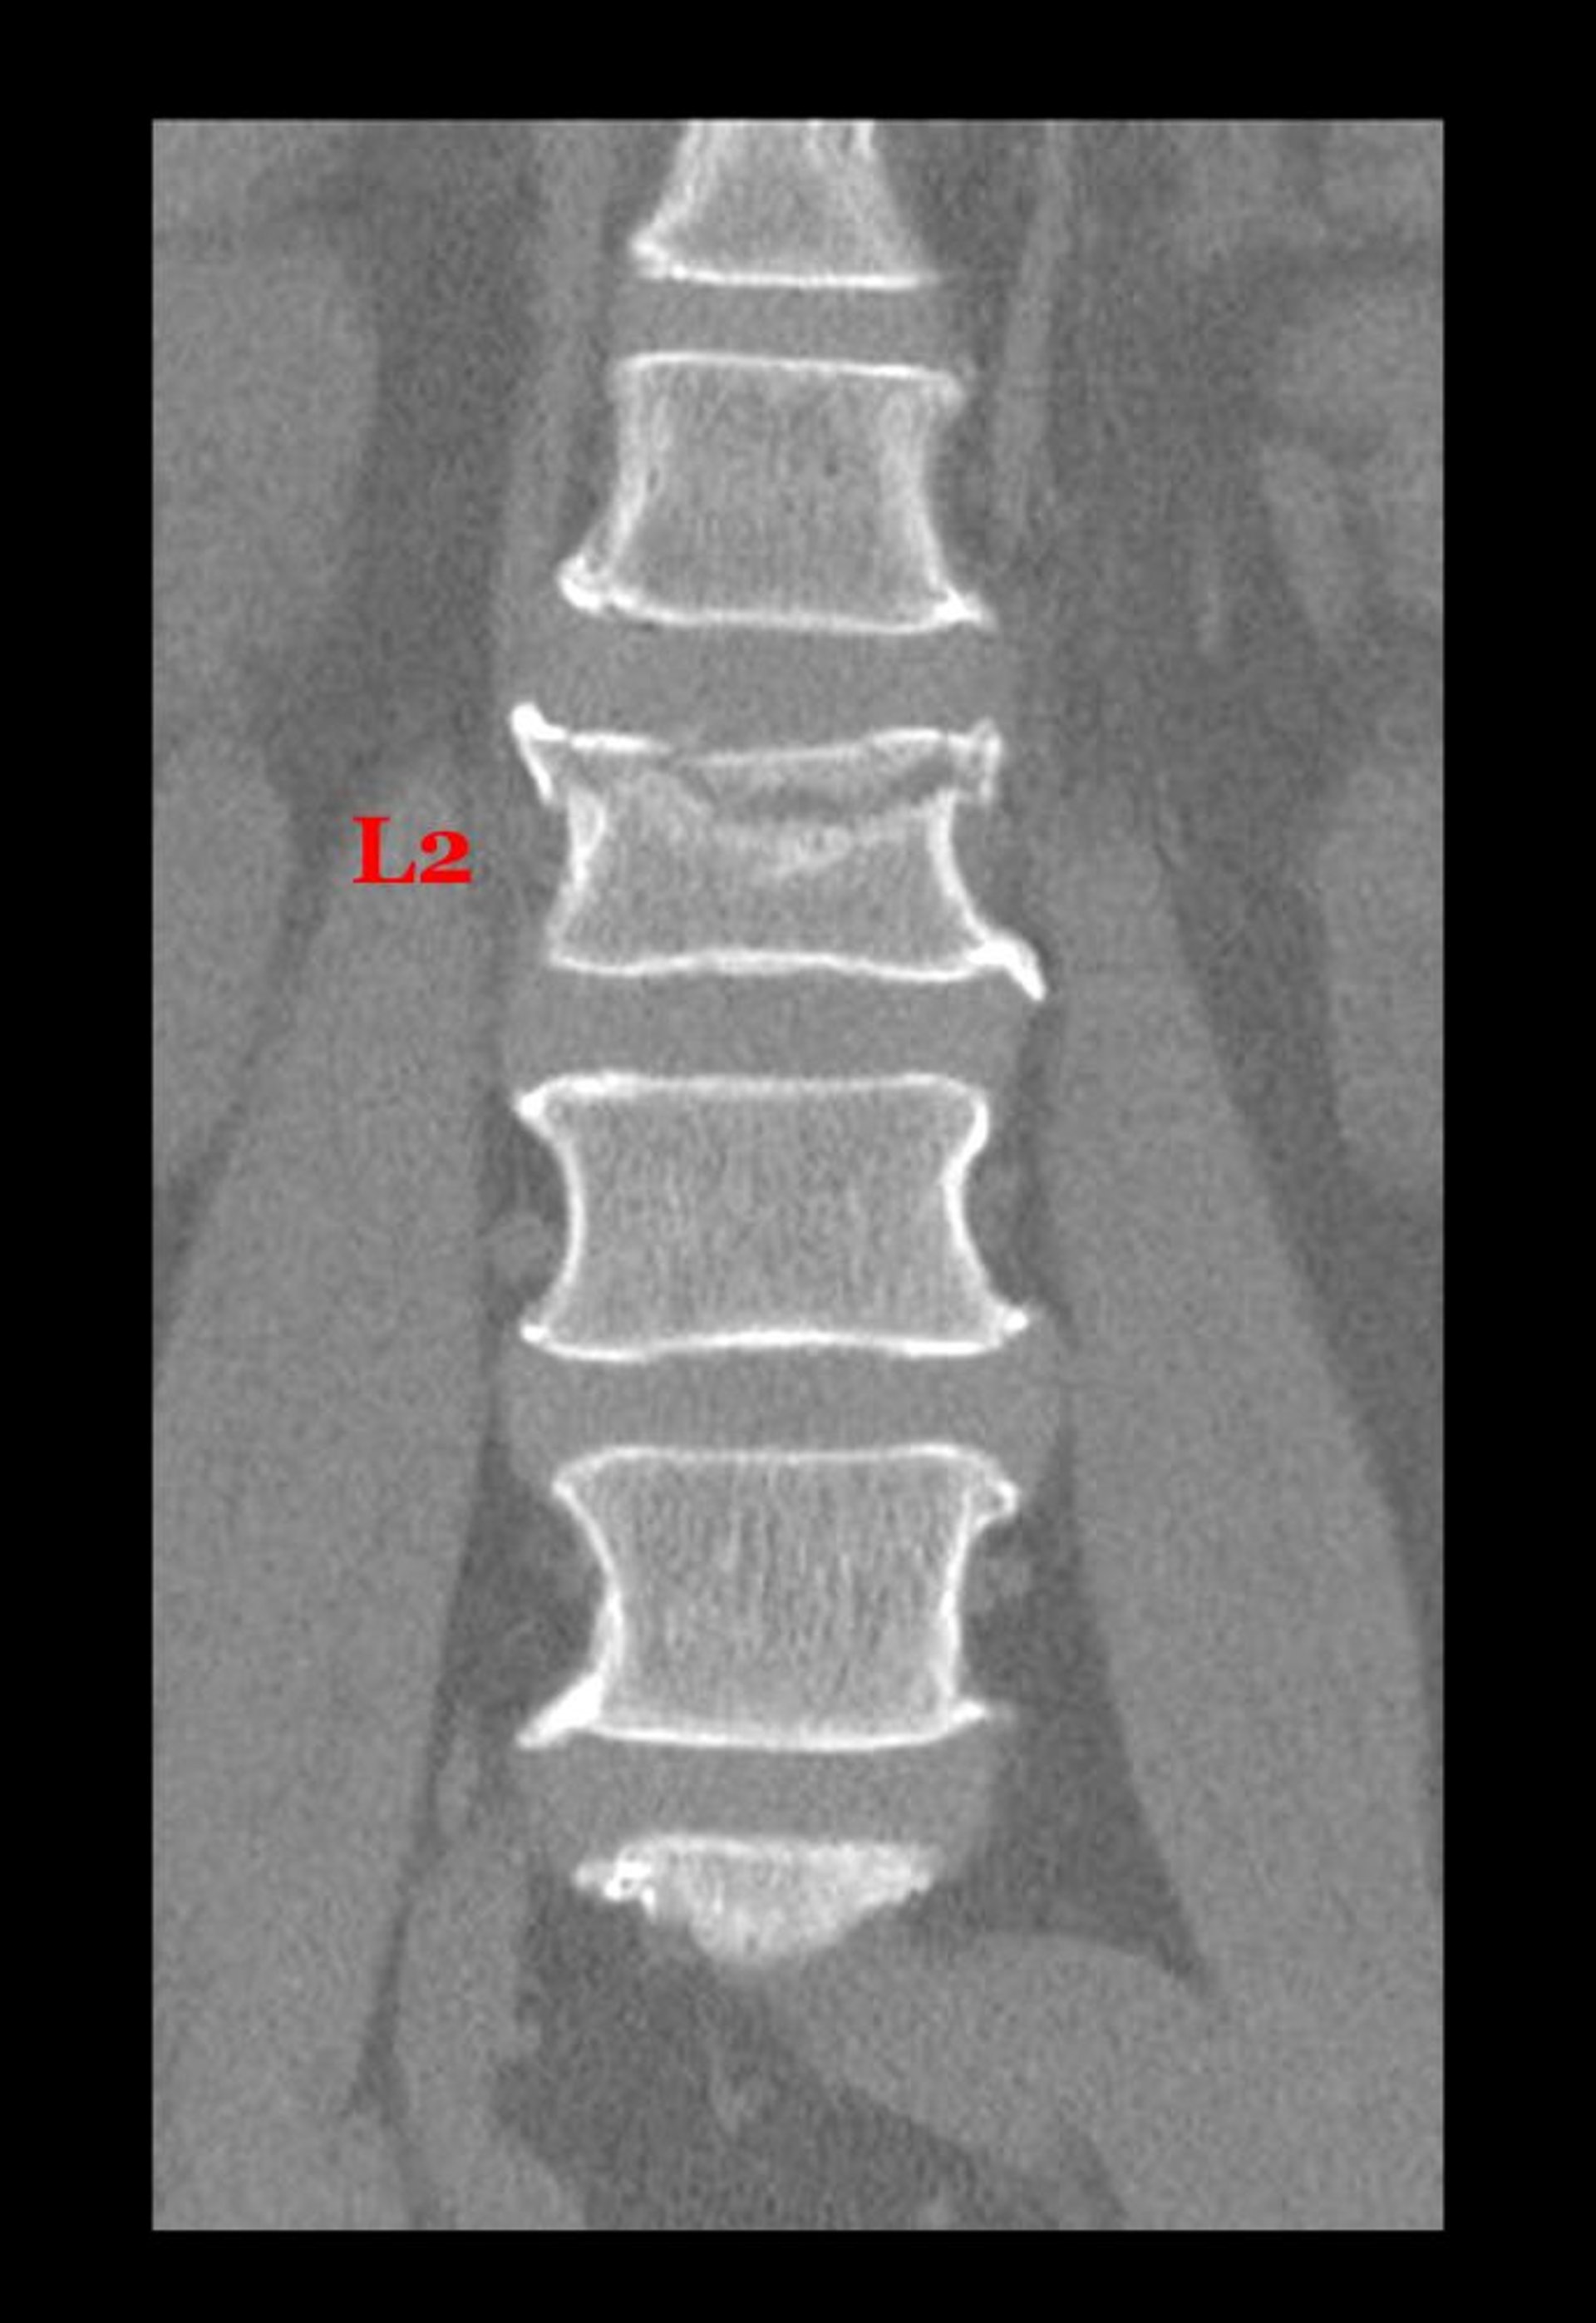

Fratura por compressão de uma vértebra lombar

Essa incidência coronal (frontal) de uma TC mostra uma fratura ao longo da face superior do corpo da 2ª vértebra lombar.